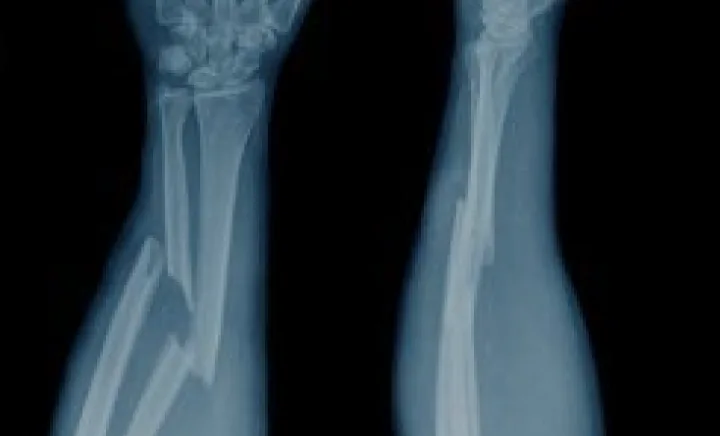

Bone Fractures

Bone fractures involve the disruption of bone structure that may influence mobility and stability. Regenerative medicine approaches using MSCs, PRP, and exosomes are explored as complementary biological support to assist natural recovery pathways.

Bone fractures involve disruption of bone structure that may influence mobility, stability, and overall functional recovery. The healing process typically requires structured orthopedic care, rest, and gradual rehabilitation. In regenerative medicine, supportive therapies such as mesenchymal stem cells (MSCs) and Platelet-Rich Plasma (PRP) are increasingly explored as complementary approaches aimed at assisting cellular signaling pathways, inflammation regulation, and tissue-support environments under medical supervision.